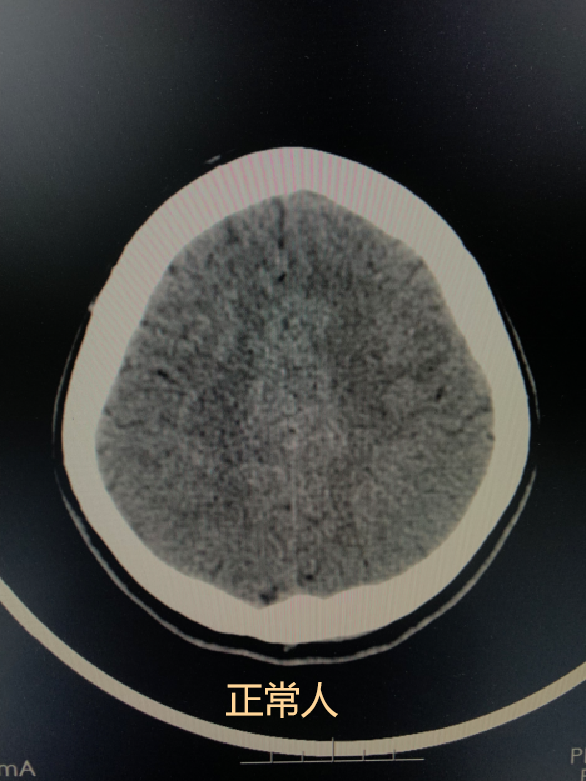

腦萎縮

之所以排在第一位,是因為一般60歲以上人群做CT檢查後經常會出現這種徵象。大部分情況下它是一種生理性改變,和人老了頭髮會變白,會有皺紋是一個道理)